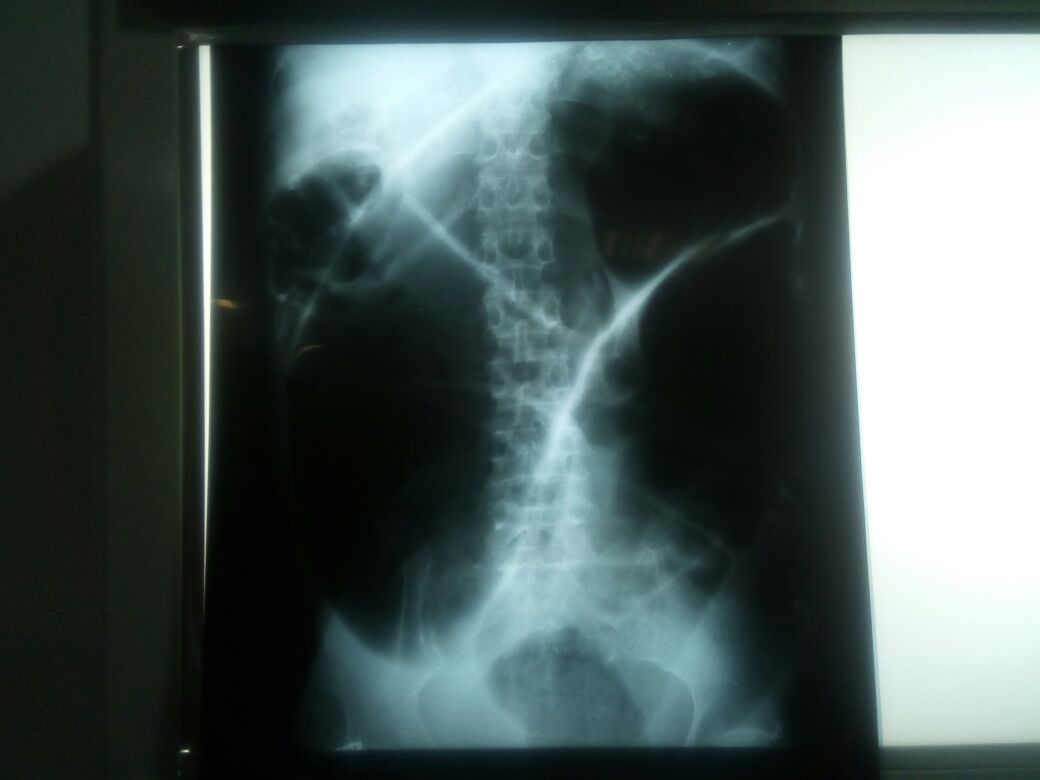

Patologías Quirúrgicas